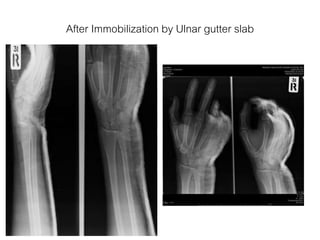

After Immobilization by Ulnar gutter slab

After Immobilization byUlnar gutter slab

Diagnosis • Close fractureshaft of 5th metacarpal bone(Proximal part) of Right hand

Management • Film – WristA-P , Lateral – Hand A-P , Oblique • Orthopedic management – Ulnar gutter slab with safe position – Allowed to return home and follow up. • Medication – Acetaminophen oral. – Tramadol oral.